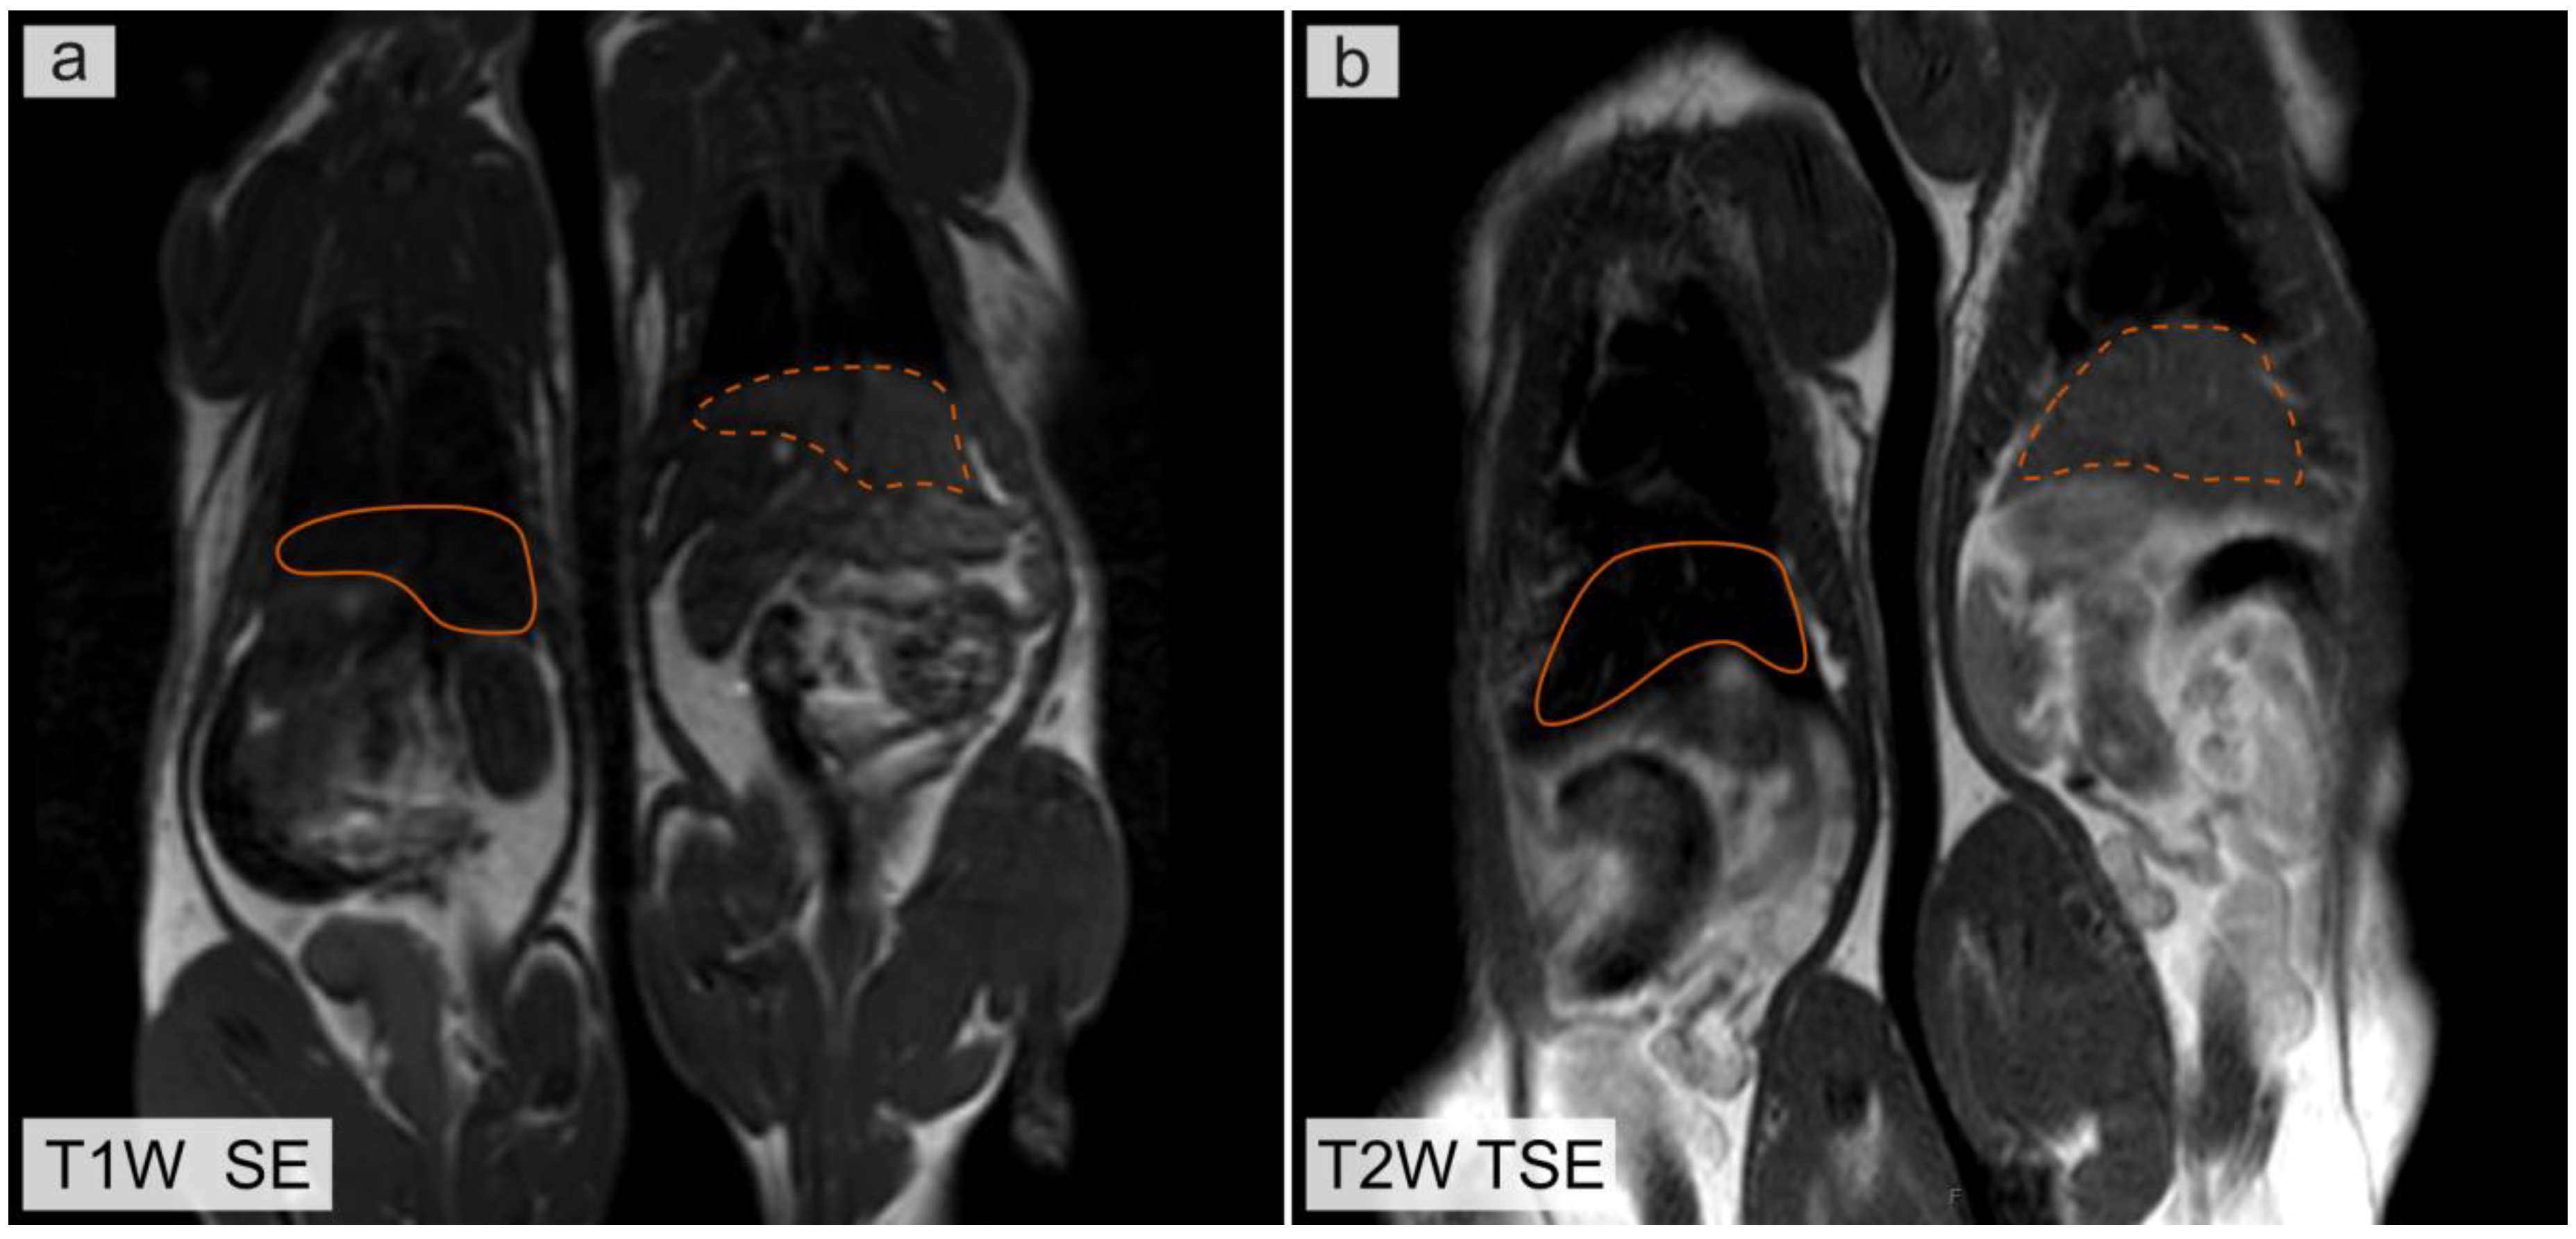

Figure 3 shows the T1 and T2 weighted MR images of rats obtained 24 h after injection of microcapsules containing magnetite nanoparticles. Solid orange lines indicate liver in a rat after microcapsule injection. Dotted orange lines indicate liver in a control rat. Magnetite distributed in liver leads to a decrease in the MR signal intensity in the region of interest (ROI) in the T1 weighted MR images (Figure 3a). This can be explained by the fact that the concentration of magnetite in the ROI was higher than 0.4 mg/mL. At high concentrations of magnetite nanoparticles, the effect of the T2 relaxation process on the measured MR signal intensity was higher than the effect of the T1 relaxation process. This leads to a decrease in the MR signal intensity in the T1 weighted images. The T2 relaxation time affects the MR signal intensity in the T1 weighted images because in clinical MRI the images are weighted by T1 and T2 but not calculated from only T1 or T2 relaxation times. Pure T1 and T2 images are not useful in clinical MRI, because the T1 and T2 values could not be applied for differential diagnosis or characterization of pathology [39].

Figure 3. Magnetic resonance (MR) images of rats obtained 24 h after injection of a microcapsule suspension. (a) T1 weighted MR image. (b) T2 weighted image. The rat on the right is a control rat, without injection of microcapsules.